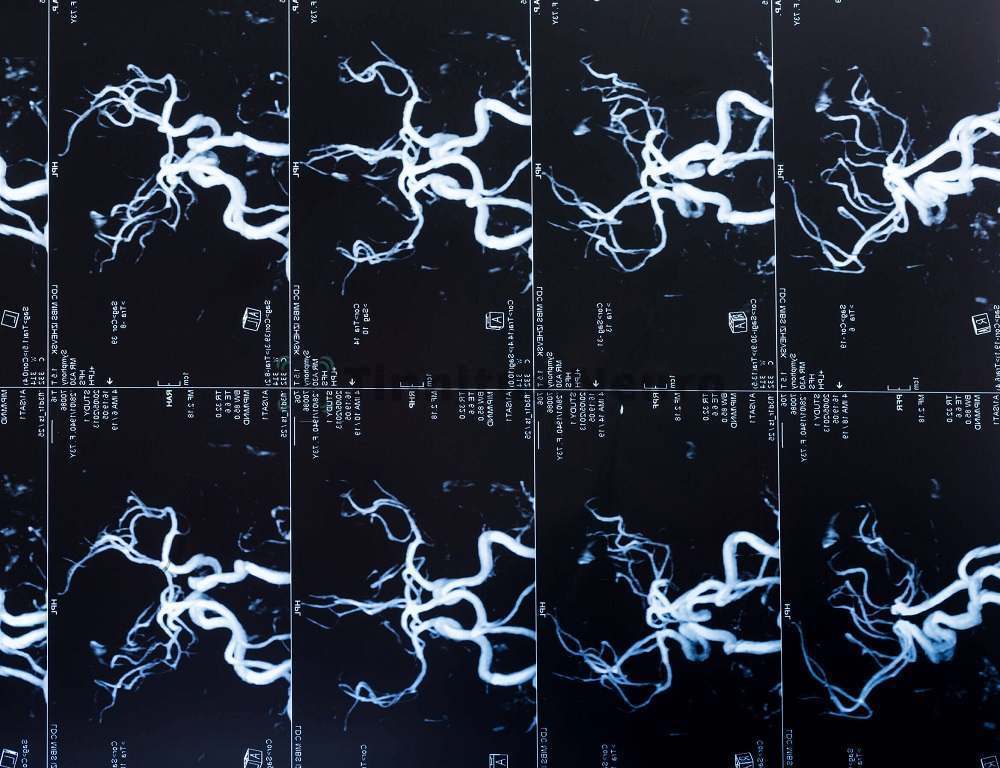

Поскольку кровеносная система расположена внутри человеческого организма, ее невозможно проверить с помощью внешнего осмотра. Для этого необходима более сложная методика, которая позволит увидеть, есть ли нарушения в работе. МРТ сосудов – эффективный способ, с помощью которого можно дать объективную оценку состояния головного мозга и шеи.

Частые головные боли, головокружение, тошнота, периодические обмороки – с этими, наиболее распространенными, симптомами врач отправляет на МРТ-диагностику. Методика основана на эффекте магнитного резонанса.

Аппарат принимает сигналы от источника, имеющие разную амплитуду. В итоге получается скан каждого слоя-среза ткани или органа, которые обследуются томографом. Картины-снимки даются в разных проекциях:

Все это в комплексе переводится в трехмерное изображение с высоким разрешением, на котором можно рассмотреть даже самые мелкие детали.

Полученная картинка сохраняется в цифровом виде – к лечащему врачу ее можно переправить по Интернету или на любом электронном носителе.